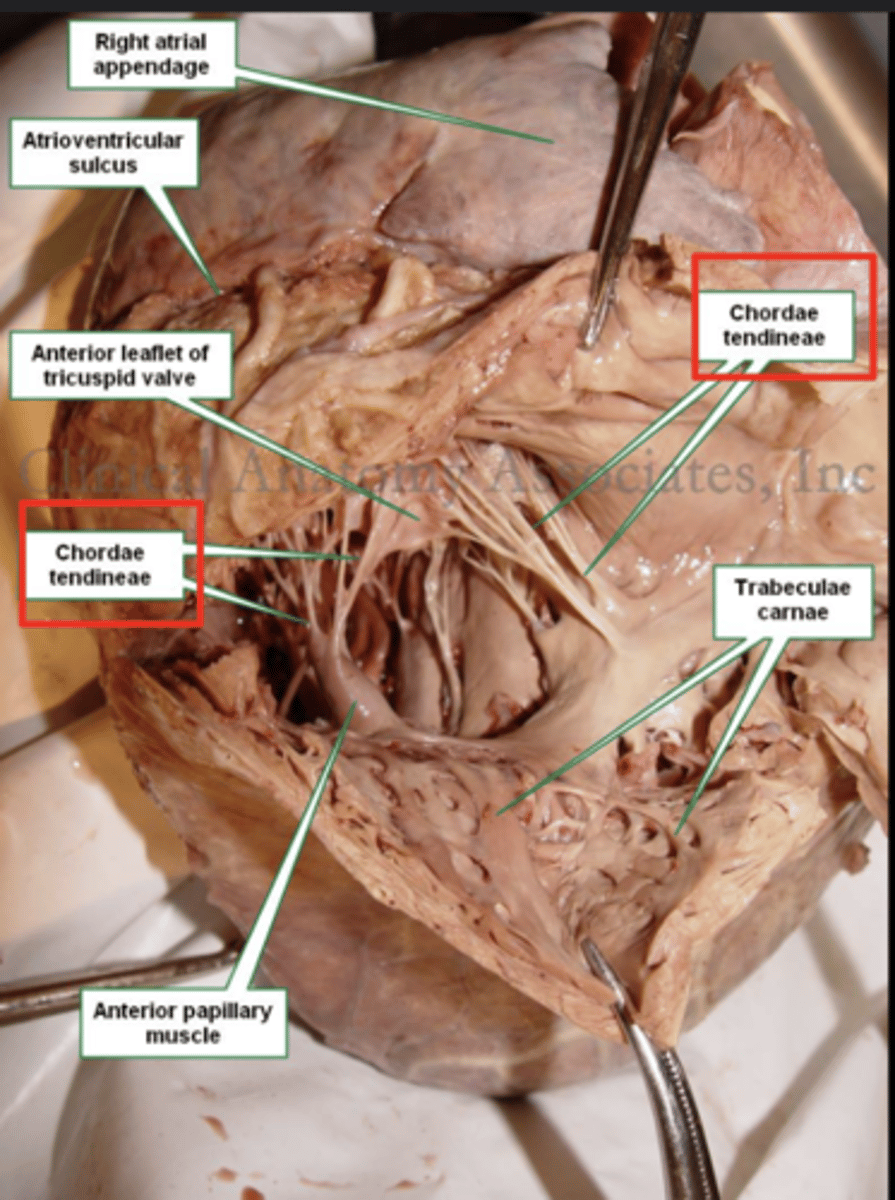

What connect the cusps of the valve a to papillary muscles in the

right ventricle?

Chordae tendinae

With the contraction of the walls of the ventricle what's the action of the papillary muscles?

contract as well

With the contraction of papillary muscles what will be happen with the valve?

Close

What role do the papillary muscles and chordae tendineae play in the function of the tricuspid valve?

During ventricular systole (contraction), the tricuspid valve closes

The papillary muscles contract at the same time as the ventricle.

This contraction tightens the chordae tendineae, pulling the valve leaflets taut and holding them in place.

This mechanism prevents the valve leaflets from prolapsing (bulging back) into the atrium under the high pressure of ventricular contraction.